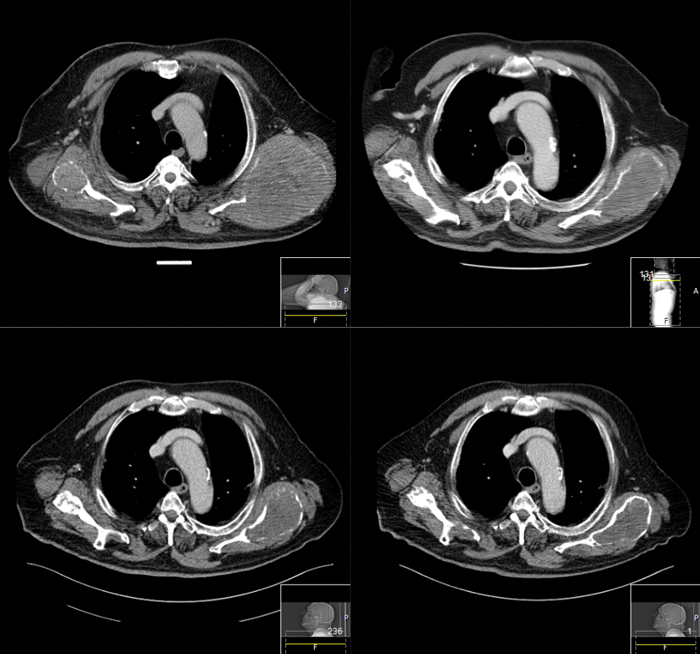

Figure 1: Patient referred for consideration of systemic therapy as iodine refractory DTC and limited response to palliative external beam radiotherapy for pain control of bilateral scapulae metastases. Images show response of scapulae metastases to lenvatinib over four years.

In all studies discussed above, the secondary endpoint of OS did not reach significance. The high rates of crossover from placebo to active drug in DECISION, SELECT and ZETA studies and the immaturity of the data at the time of reporting probably contribute to the difficulty in identifying an OS advantage. However, without evidence of this, the decision to start a MKI should be made with a clear goal of treatment carefully weighing up the likely clinical benefit over toxicities for the individual patient (see Figure 1).